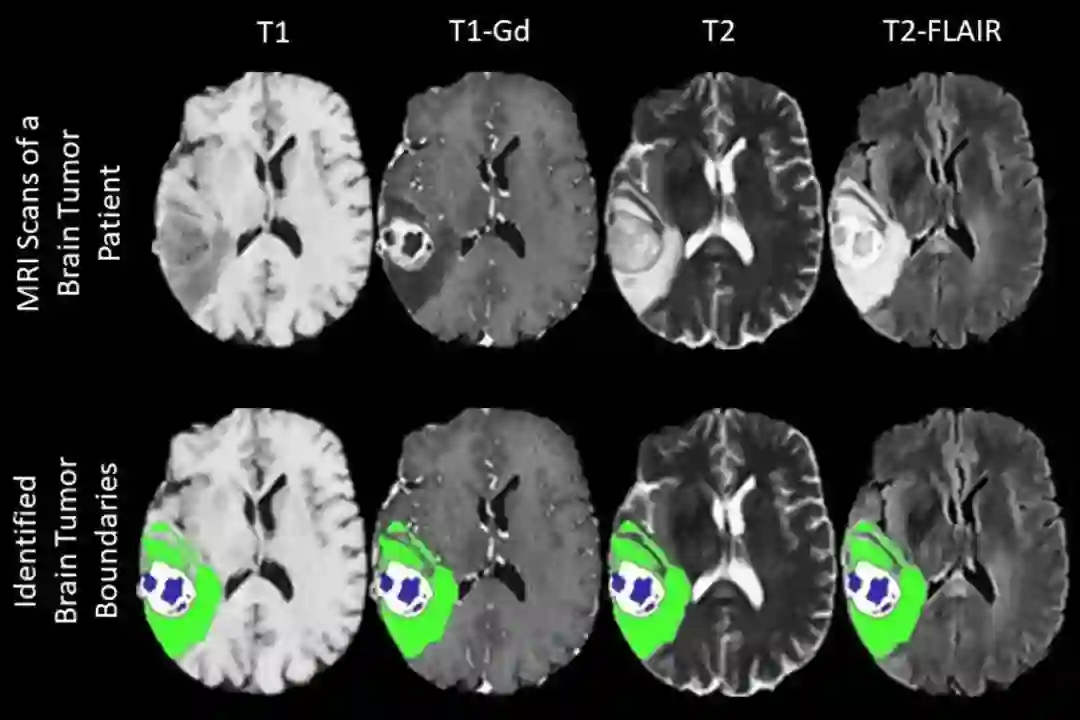

以训练机器学习算法来识别医学图像中脑肿瘤的边界

宾夕法尼亚大学医学院放射学和病理学讲师 Spyridon Bakas 表示,过去 6 年,他帮助汇编了可用于 AI 训练的最大脑瘤图像数据集之一,该数据集包含了大约 600 名患者的图像,但新的联邦学习项目将大大扩展这一数字。